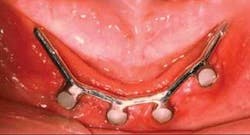

Q If you were edentulous and had adequate bone for standard-diameter implants, which would you have: conventional 4 mm-diameter implants or the now popular small-diameter implants starting at 1.8 mm in diameter?A Putting the example in my own body does not change my attitude about the question. It just makes me compare the procedures from all standpoints. I have placed implants in and restored hundreds of edentulous patients with conventional-diameter implants, ring retainers, ERAs, bar and clip restorations, and many other attachments. Very few of the restorations have failed, and almost 100 percent of the patients have been satisfied with the treatment.On the other hand, the previously mentioned treatments are expensive, potentially painful, and success is laboratory-dependent. You and I can place small-diameter implants such as IMTEC Sendax MDI or Dentatus Atlas in a few minutes, without a surgical flap, relatively painlessly and inexpensively, and the implants can be loaded the day they are placed (see Figures 1 and 2).

I must admit, as a prosthodontist interested in the best quality I can deliver for the money, the conservative, noninvasive, small-diameter (mini) implant is very desirable for simple restoration of edentulous jaws. I have had great success with these implants over the approximately seven years I have placed and restored them.

Unless the patient prefers a more stable, rigid attachment of the prosthesis, I lean toward using more minis and fewer conventional-diameter implants.